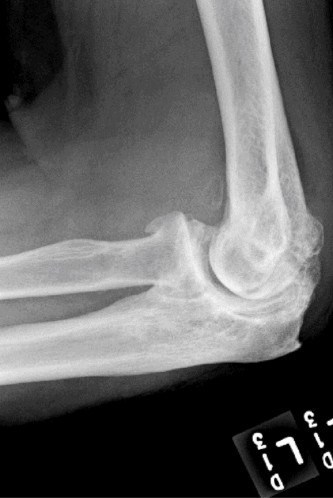

Understand common complications associated with performing surgery for scapulothoracic bursitis? CASE 33 A 42-year-old female presents to the office for follow up after sustaining a minimally displaced radial head fracture 3 months prior. She states she was initially treated in long-arm splint by the ER and did not follow up with an orthopaedic surgeon until now. Per her report, she removed the splint 4 weeks after the injury, but did not move her elbow due to pain. She now has no pain but is unable to reach that hand to her face or head. The remaining history is significant for previous ulnar nerve surgery for which she is unable to provide details. On physical examination, her upper extremity is normal except for limited flexion/extension, measured to be 80 to 50 degrees by goniometer. In addition, she has a well-healed surgical incision about the medial elbow, consistent with a previous surgery on her ulnar nerve. Her images are shown (Figs. 2–82 to 2–84).

Figure 2–82

Figure 2–83

Figure 2–84

The correct answer is (A). Classification of post-traumatic elbow stiffness allows for better understanding of the disease and allows the clinician to treat the underlying cause of the joint contracture. Intrinsic causes include: any problem within the joint such as incongruency, loose bodies, or severe osteoarthritis. Extrinsic causes include capsular tightness, muscle contracture, heterotopic ossification, and skin contractures. Early is defined as within 6 months of the injury while late is considered to be greater than 6 months after the injury. Patients that present in the early time frame have a significantly better chance at having a good result both from nonoperative and operative treatment.